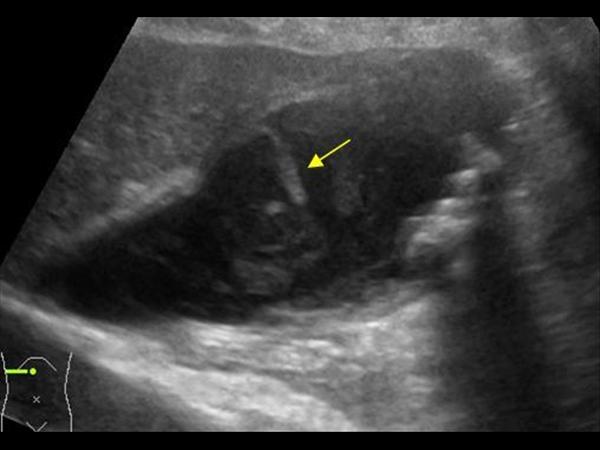

Viêm túi mật

» Thông tin: Nữ giới – 87 tuổi.

» Lâm sàng: Đau mạn sườn phải / Sốt.